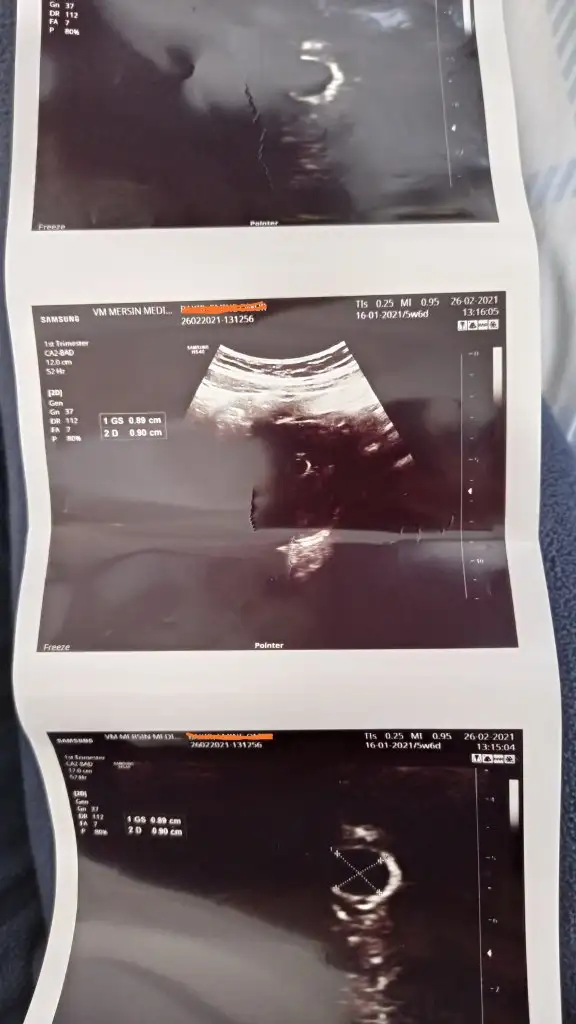

Selam arkadaşlar bugün ilk doktor kontrolüme gittim karından baktı kesemiz gözüktü 7.2mm satla uyumlu 5 haftalık2 hafta sonra kalp atışını duyarız dedi karından anca o zaman gözüküyor şimdi bekle bakalım 2 hafta kese sağlıklı normal gözüküyor dedi bir takım tahliller istedi onları pazartesi devlette yaptıracağım. Folik asite devam dedi, kanama falan durumunda haberim olsun dedi bir şikayetin yoksa 2 hafta sonra görüşürüz dedi bizden haberler böyle bekleyenler de en kısa zamanda mutlu haberleri alırlar inşallah